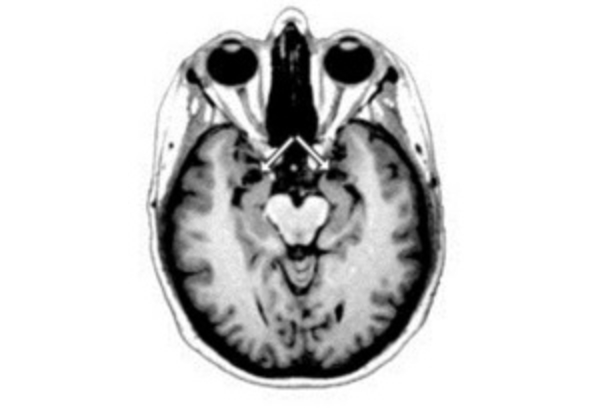

В ходе каждой сессии ученые наблюдали за активностью мозга своих подопечных при помощи компьютерного томографа и диффузионной тензорной визуализации и проверяли их умственные способности при помощи набора нейропсихологических тестов.

В частности, активность среднего мозга – центра первичной обработки информации – была значительно снижена, а взаимосвязи между его компонентами были ослаблены. Аналогичные изменения происходили и в нейронах, объединяющих средний мозг с префронтальной корой – центром хранения информации и обработки сложных поведенческих реакций.

По словам биологов, часть этих изменений так и не исчезла через 2 года после возвращения контрактников на родину – связь между средним мозгом и префронтальной корой так и не восстановилась за 2 года после экспедиции.